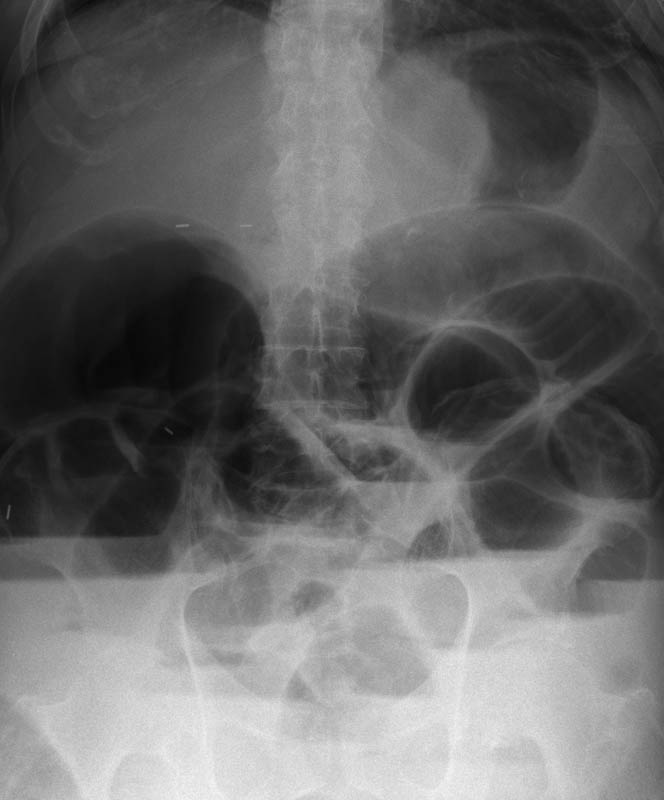

Diverticulosis de colon.

Diverticulosis de colon. Megacolon.